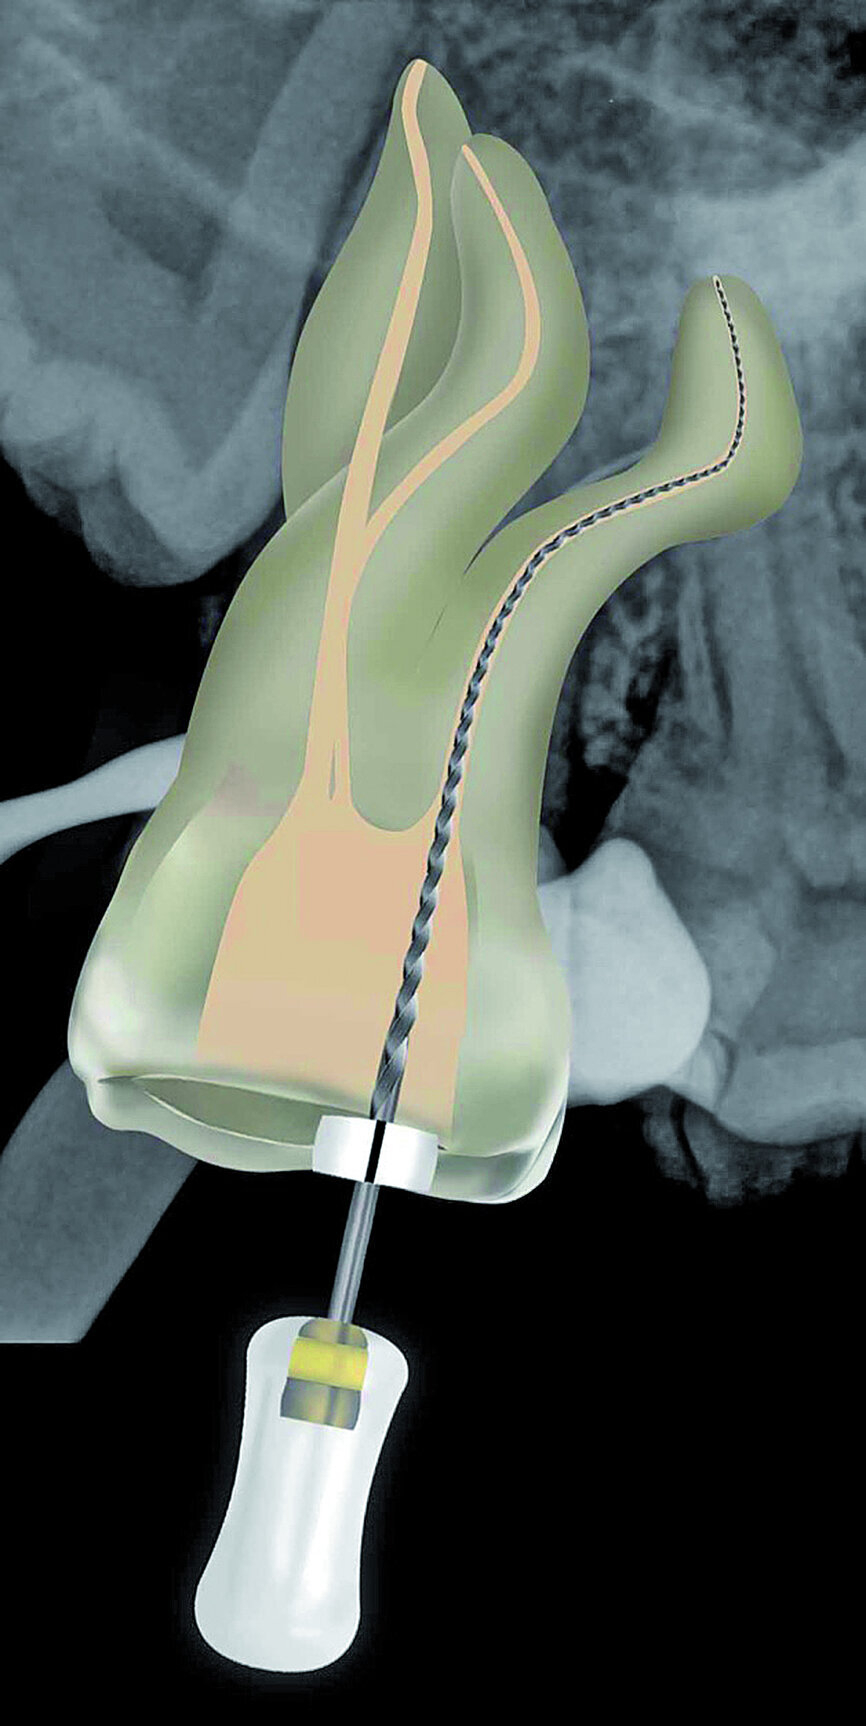

Fig. 23: A ProGlider was used in a rotary motion to expand the glide path in the palatal root canal.

Fig. 24: A ProGlider, converted to a manual file, was used to expand the glide paths in the two buccal root canals.

The pulp chamber was filled with Glyde (Dentsply Sirona) before the canals were carefully negotiated to full working using pre-curved size 08 K-Files (Fig. 19). Working length measurements obtained from an electronic apex locator reading corresponded with the lengths obtained from the 3D Endo Software. These measurements were also confirmed radiographically (Fig. 20). A reproducible glide path was prepared in each root canal system with the size 08 K-File in an M4 Reciprocating handpiece (Sybron Endo; Fig. 21), followed by making a size 10 K-File ‘super loose’ (Fig. 22). A ProGlider (Dentsply Sirona) was used in a rotary motion to expand the glide path in the palatal root canal (Fig. 23). Considering the sharp and severe curvatures in the two buccal canals, it was decided to convert the ProGlider instrument into a manual file to expand the glide path in these tortuous canals with more safety (Fig. 24). The manually adapted ProGlider was used in a balanced force motion up to working length. In addition, to create more safety during the canal preparation of the two challenging buccal root canals, it was also decided to use the reciprocating WaveOne Gold Glider (Dentsply Sirona; Fig. 25), after the ProGlider instrument to further expand the glide paths. The WaveOne Gold Glider was used in 4–8 backstroke brushing motions from working length, in the two buccal root canal systems.